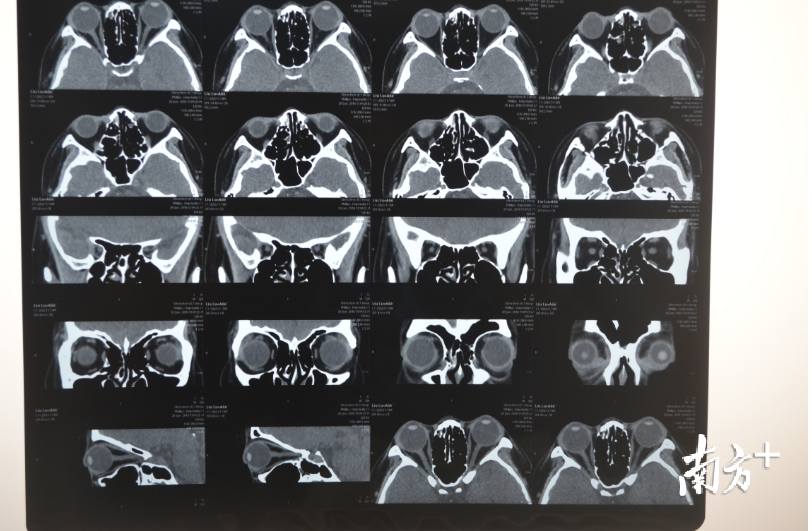

刘桂琴介绍,高度近视者之所以会感觉眼球突出,并不是眼球的位置发生了变化,主要是眼球变长了。“正常眼球接近圆球形,高度近视的人用眼过度后,眼球周边肌肉会变紧张,压迫眼球,导致眼球前后轴变长,就会出现眼睛变形,眼球前面就会突出来,像个‘金鱼眼’。”刘桂琴说,眼球的变长也是通过B超、CT或MRI检查出来的,患者自己感觉不到眼球变长,只感觉到眼球向前鼓出来了。